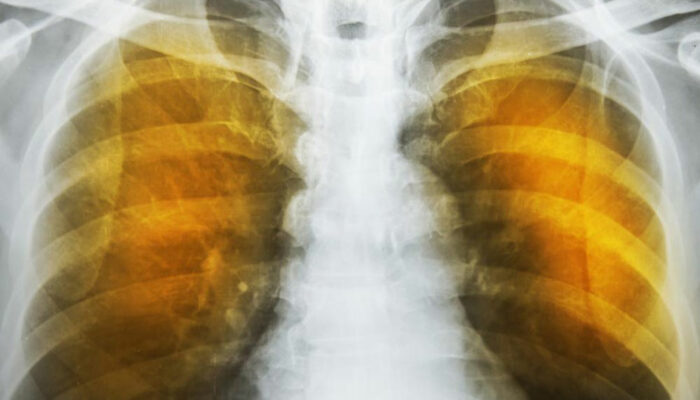

Emphysema is an oppressive respiratory disorder which results from the disintegration of the alveoli, i.e., the tissues where the interchange of gas with blood takes place. Destruction in any large scale will reduce the gas transfer area and the process of gas transfer itself, leading to oxygen starvation or hypoxia.

Another complication is the alveoli becoming weaker, and then starting to break. When this assumes larger scale, vacant spaces are formed called bullae. This reduces the gas transfer area as well as the capacity of the lung to expand. These are often have to be surgically removed to allow more space for the lung to expand. In the ultimate case, lung transplant becomes the only choice. Another scenario is a large-scale disintegration of alveoli that can cause pneumothorax, which is a condition in which the chest cavity is filled with air and the lungs collapse. This is a very serious condition if not fatal.